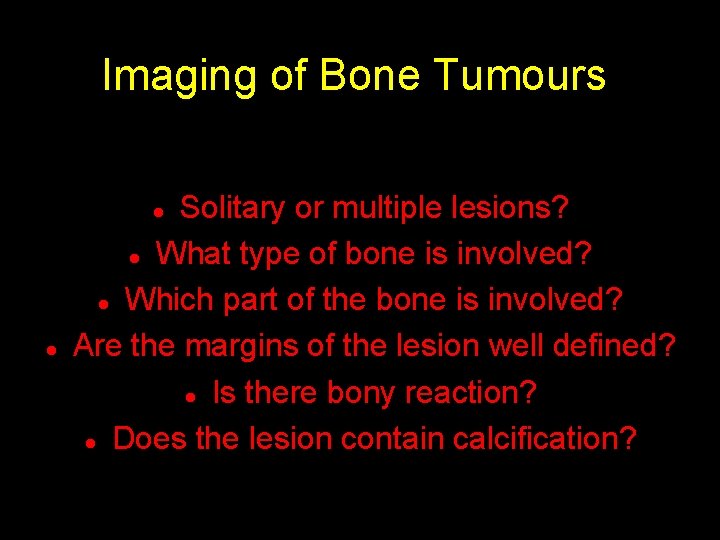

Imaging of Bone Tumours Solitary or multiple lesions? l What type of bone is involved? l Which part of the bone is involved? Are the margins of the lesion well defined? l Is there bony reaction? l Does the lesion contain calcification? l l